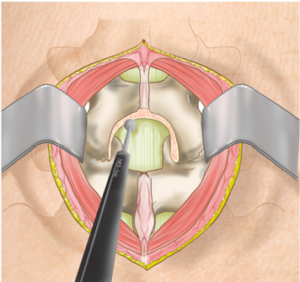

脊柱管狭窄症の手術は、大きく分けて「除圧術」と「固定術」の2種類があります。

固定術は、背骨の不安定性が強い場合に行われます。

金属のスクリューやロッド、人工骨を使って背骨を安定させる方法で、前方から行う方法と後方から行う方法があります。

XLIFやOLIF、CBT法など、体への負担を抑えた術式も開発されています。